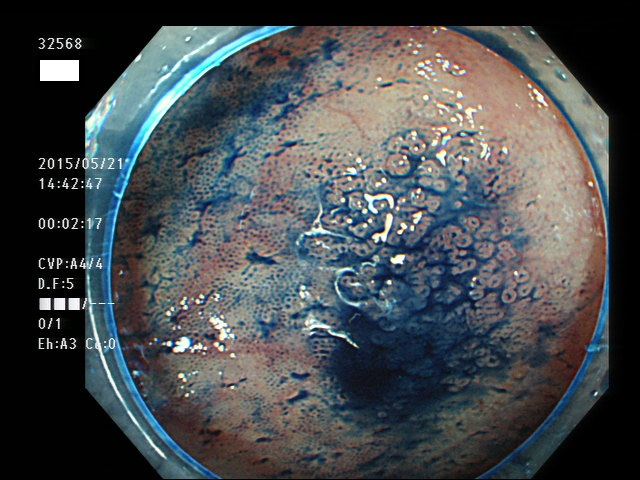

上記100名より抽出した平坦・陥凹型腺腫(=癌化の危険が高いが見落としやすい病変)の内視鏡写真

32550 32553 32555 32556 32558 32559 32560 32562 32563 32564 32568 32569